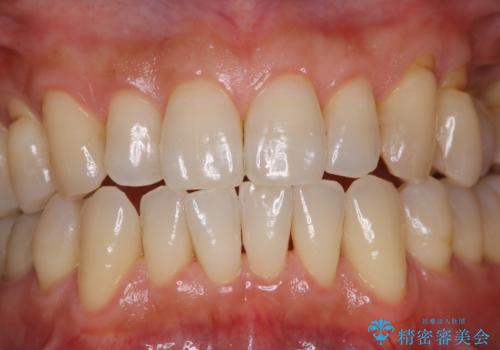

PMTC30分コースを行いました。

矯正治療中も清潔な口腔内を保つことは、とても大切です。そのため、定期的に専門的な機械・材料を使用したProfessinnalcleaning(pmtc)を行うことがおススメです。